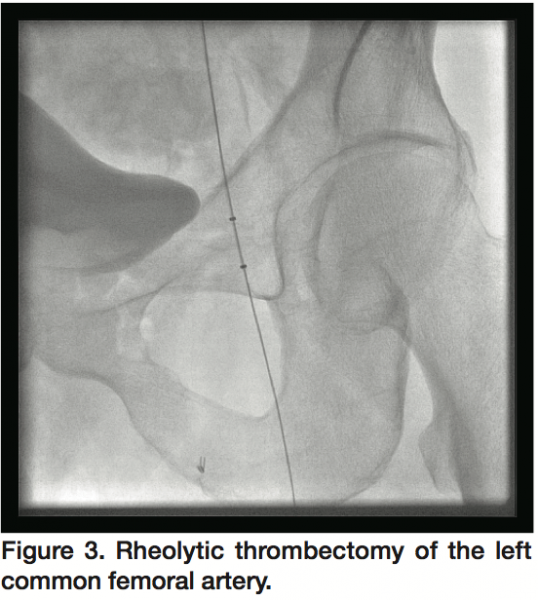

Repeat vascular testing confirmed a significantly diminished left ankle-brachial index of 0.38. A CT angiogram with runoff of the left lower extremity demonstrated complete occlusion of the left common femoral artery with collateral filling of the superficial femoral artery. He was then referred for left lower extremity angiogram and percutaneous intervention.

Access was obtained in the right common femoral artery and selective left external iliac artery angiogram was performed, which confirmed hazy thrombotic occlusion of the left common femoral artery at the site of AngioSeal (St. Jude) deployment with reconstitution at the bifurcation of the left superficial femoral and profunda femoris arteries (Figure 2). With the support of a 4 Fr glide catheter, an angled Glidewire (Terumo Medical) was used to cross the occlusion into the distal superficial femoral artery (SFA) with a gradient of 50 mmHg across the occlusion. Rheolytic thrombectomy was then performed using an AngioJet catheter (Medrad Interventional) with multiple runs into the SFA (Figure 3) and profunda femoris artery with improvement in flow across the lesion but persistence of residual thrombus. The glidewire was then exchanged for a Confianza Pro 0.014 mm wire (Asahi Intecc) and laser atherectomy was performed using a 1.7 mm Turbo Elite laser catheter (Spectranetics) utilizing fluence/rate settings of 40/40, 60/60, and 60/80 serially (Figure 4) with further improvement of flow across the left common femoral artery.